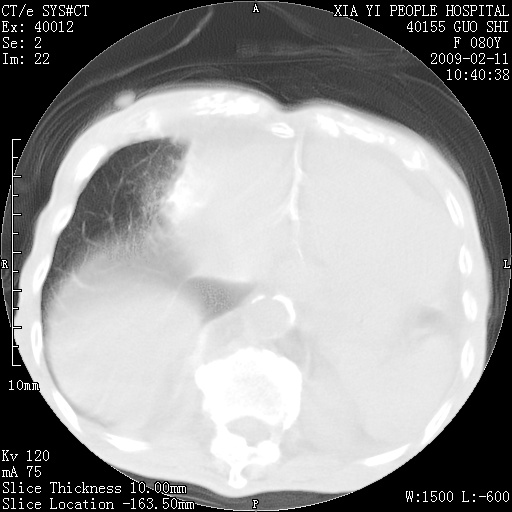

以下是引用随光逐影在2009-2-16 16:34:00的发言:[br]1)考虑右前纵隔皮样囊肿。2)双侧少量胸腔积液。

以下是引用zjzjr在2009-2-16 17:30:00的发言:[br]支持囊性畸胎瘤 双侧少量胸腔积液。